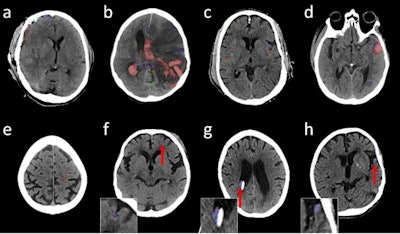

Illustrative head noncontrast CT axial images with predicted and reference segmentations; red shows true-positive, blue shows false-negative, and green shows false-positive voxels. (A-E) are high-confidence true-positive studies, (F) and (G) are low-confidence true-positive studies and (H) is a low-confidence false-negative result. Arrows and insets are shown for (F-H) to improve visibility of the overlays. The shunt adjacent and medial to the hemorrhage in (F) and the head tilt in (G) may have affected the confidence scores. Images and caption courtesy of the RSNA.The research included 46,057 CT studies; data was categorized as "internal" (for training of the model) and "external" (for calibration and evaluation of it). The algorithm's performance was measured using area under the receiver operator characteristic curve (AUC ROC) analysis and report turnaround time. The authors also estimated two confidence scores (calibrated classifier [CC] and Dempster-Shafer [DS], both based on a scale of 0 to 1, with higher scores denoting higher confidence).

AUC ROC measures were high -- particularly with the internal, or training, dataset -- demonstrating good performance from the algorithm in detecting, localizing, and subtyping intracranial hemorrhage.

The CC confidence score was 0.93 and the DS score was 0.92 for the internal dataset and 0.88 and 0.89 for the external dataset. The group also found that the AI algorithm showed potential to help reduce report turnaround time by 25% to 27%.